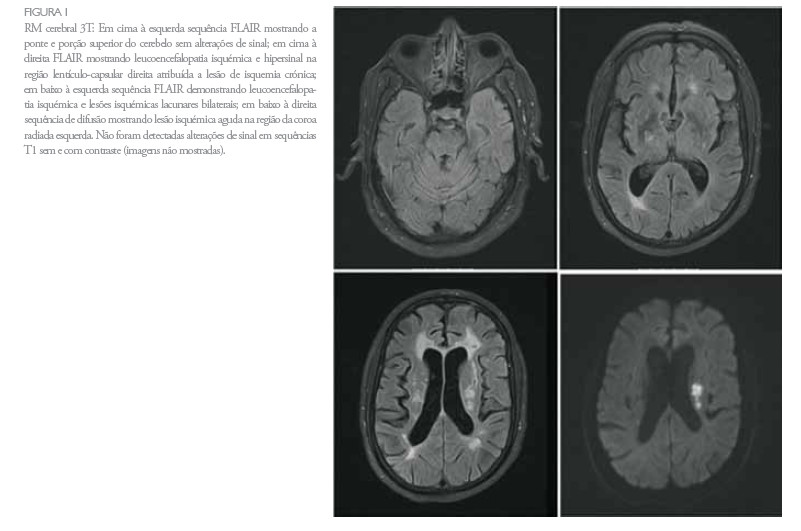

Para esclarecimento etiológico deste quadro, realizou: -eco-doppler cervical e transcraniano: placas ateroscleróticas junto à bifurcação das carótidas comuns e início da interna direita, sem estenoses significativas (20-25% à esquerda e 25-30% à direita). Artérias vertebrais e basilar com fluxos sanguíneos conservados. Sinais hemodinâmicos compatíveis com estenoses superiores a 50% na cerebral posterior esquerda (porção P2) e na porção terminal da carótida interna direita e inferior a 50% na cerebral média direita. -RMN cerebral (Figura 1): lesão isquémica recente na coroa radiada esquerda; lesões isquémicas não recentes nos gânglios da base à direita e em ambas as coroas radiadas e cápsulas externas; leucoencefalopatia isquémica. Em T2 e FLAIR, observou-se hipersinal focal na ponte de isquemia crónica de pequenos vasos, mas sem enfarte franco. As sequências de angio-RM do polígono de Willis mostraram alterações consistentes com as demonstradas pelo eco-Doppler. -exame do LCR: proteínas elevadas (0,86 g/l), 10 células µ/l, representando ligeira dissociação albumino-citológica.

A síndrome de Fisher-Bickerstaff cursa tipicamente com dissociação albumino-citológica2,3 e positividade para o auto-anticorpo anti-GQ1b2 (em 85% dos casos5,6). Na maioria dos doentes, os estudos imagiológicos não revelam alterações específicas2, tal como no doente que apresentámos. Porém, em alguns, a RMN demonstra alterações no mesencéfalo, cerebelo ou pedúnculo cerebeloso médio7, que geralmente surgem hiperintensas em T2 ou, mais comummente, como áreas captantes de contraste em T12. O diagnóstico diferencial inclui uma lesão aguda do tronco cerebral, principalmente encefalite do tronco3. Na síndrome de Fisher-Bickerstaff, o sintoma inicial mais frequente é a diplopia, seguida de perturbações da marcha7. Sintomas de apresentação menos comuns incluem parésia facial, ptose palpebral, fraqueza muscular dos membros, disfagia, fotofobia, hipovisão, tonturas e cefaleias2. Neste doente, os sintomas de apresentação foram disartria e parésia facial. A oftalmoplegia é o achado mais prevalente e consistente na fase aguda da doença19, sendo, na maioria dos doentes, bilateral e relativamente simétrica2. A ataxia pode ser bastante severa, originando uma perturbação da marcha; asua patogénese ainda não está completamente estabelecida, acreditando-se que possam estar implicados mecanismos periféricos (proprioceptivos) e centrais (cerebelosos)2. A maioria dos doentes recupera de forma espontânea e completa dentro de 2 a 3 meses após o início da doença2. O tempo médio desde o começo dos sintomas neurológicos até o início da recuperação é 12 dias para a ataxia e 15 para a oftalmoplegia. O tempo médio para a resolução completada a taxia é de 1 mês e de 3 meses para a oftalmoplegia. Aos 6 meses após o início da doença, os doentes não apresentam normalmente limitações significativas na actividade. A rapidez de recuperação é independente da idade do doente, sexo, evidência de infecção precedente, grau de incapacidade no pico da doença ou tempo de latência até ao pico8. O tratamento com imunoglobulinas intravenosas não tem habitualmente efeito no resultado global, provavelmente porque os doentes tipicamente têm uma boa recuperação espontânea9. É difícil estabelecer uma relação directa entre a recuperação neurológica deste doente e a aplicação da imunoglobulina, não se podendo, contudo, excluir a sua contribuição. Um programa adequado de reabilitação multidisciplinar é fundamental, sendo mais importante do que a imunoterapia. O programa de reabilitação tem como objectivos auxiliar na regressão dos sintomas, prevenir as complicações da doença e compensar os défices funcionais e deve ser começado numa fase precoce da doença, assim que a situação clínica o permita. Na fase aguda, a intervenção da Medicina Física e de Reabilitação (seja através de Fisioterapia ou terapia da Fala) visa a prevenção e o tratamento de complicações, muitas das quais associadas à imobilidade: retracções músculo-tendinosas, fenómenos tromboembólicos, complicações respiratórias (atelectasias, infecções respiratórias), úlceras de pressão, úlceras de córnea (sequelares a não encerramento palpebral completo), disfunção autonómica e problemas de deglutição. Posteriormente, visa o tratamento do défice motor (parésia facial), ataxia, anartria e disfagia10. No caso do doente descrito, o prognóstico funcional está agravado pela concomitância de doença vascular cerebral marcada. O caso acima descrito realça ainda a importância de uma colaboração estreita entre a Neurologia e a Medicina Física e de Reabilitação.